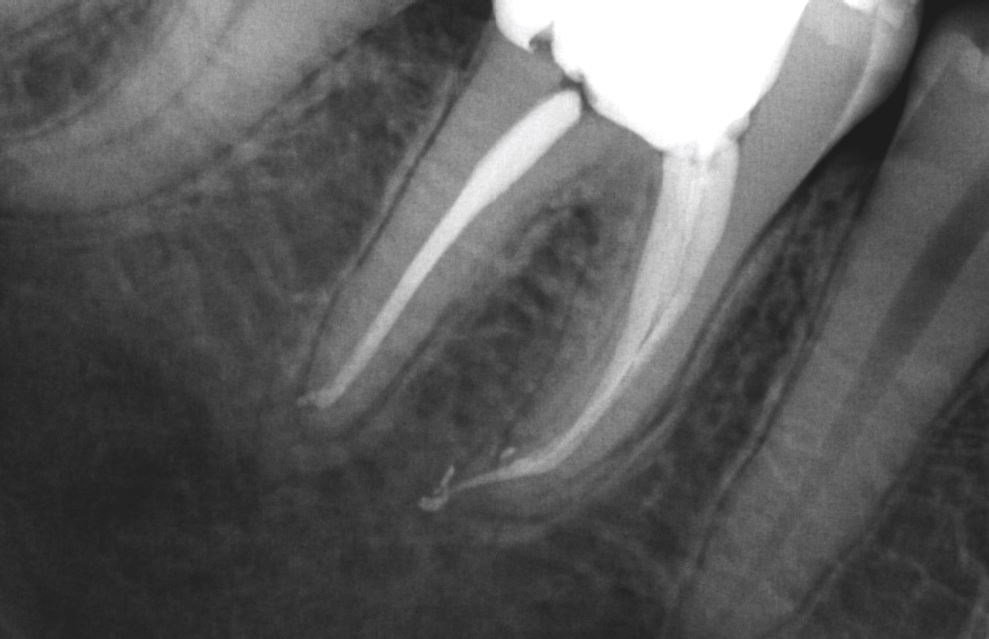

L’endodontie est une spécialité de chirurgie dentaire. L’endodontiste traite les maladies de l’intérieur de la dent. Le terme endodontie vient de «Endo» qui signifie intérieur» en grec et «dontie» signifiant la «dent». L’endodontie consiste en la prévention, le diagnostic et le traitement des maladies de la pulpe et du péri-apex (desmodonte et os alvéolaire). Elle sert à transformer une dent pathologique en dent saine, sans symptôme et fonctionnelle.

Le traitement endodontique ou canalaire a pour but de préserver les dents naturelles et à éviter les implants et les prothèses.

endodontie photo